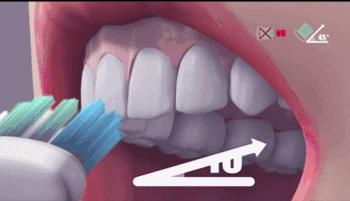

每天除了坚持使用巴斯刷牙法刷牙,还要正确使用牙线以及冲牙器进行彻底清洁,保持种植体周围卫生,才能使种植牙使用寿命更长哦。